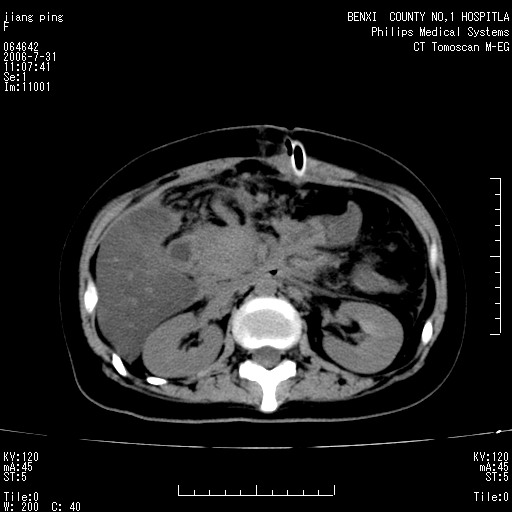

以下是引用晓杰在2006-8-1 9:01:00的发言:[br]支持营养不良导致脂肪肝。[br]胰头增大界限不清,考虑为胰腺炎破坏十二指肠粘膜、肠壁增厚、肠腔狭窄,并与胰头粘连所致

以下是引用jiajie在2006-7-31 20:34:00的发言:[br]支持营养不良导致脂肪肝。[br]胰头增大界限不清,考虑为胰腺炎破坏十二指肠粘膜、肠壁增厚、肠腔狭窄,并与胰头粘连所致。